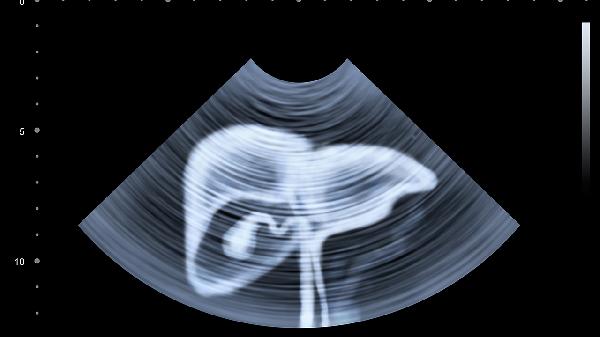

如果同时出现食欲减退、莫名消瘦、右上腹隐痛等情况,建议尽快做肝功能检查和腹部超声。

每年做一次肝功能检查和肝脏超声,40岁以上建议增加甲胎蛋白检测。有肝病家族史的人群要缩短检查间隔。